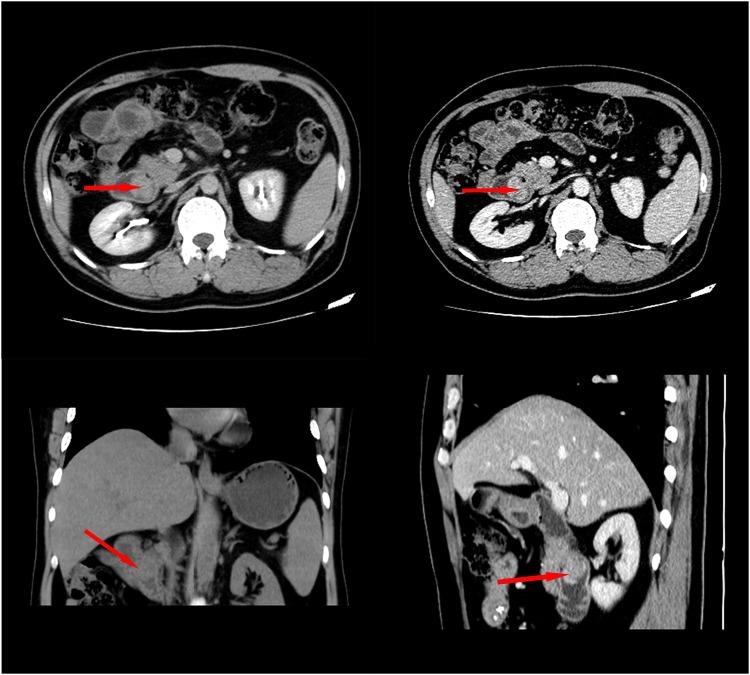

CASE PRESENTATION

In this report, a 48-year-old Chinese man was admitted to our hospital with symptoms of melena. The patient underwent choledochectomy and choledochaljejunostomy for obstructive jaundice 8 years before admission. Endoscopic examination after admission confirmed a mass located at the duodenal papilla. Then, the duodenal papilla and tumor resection were performed, and the histopathology report confirmed the diagnosis of UPS. The patient refused further treatment and died 2 months later due to local recurrence and intrahepatic metastasis.

病例报告

在本报告中,一名48岁的中国男性因黑便症状入院。该患者在入院前8年因梗阻性黄疸接受了胆总管切除术和胆总管空肠吻合术。入院后内镜检查证实十二指肠乳头处有一肿块。随后,进行了十二指肠乳头和肿瘤切除术,组织病理学报告确诊为UPS。患者拒绝进一步治疗,2个月后因局部复发和肝内转移死亡。